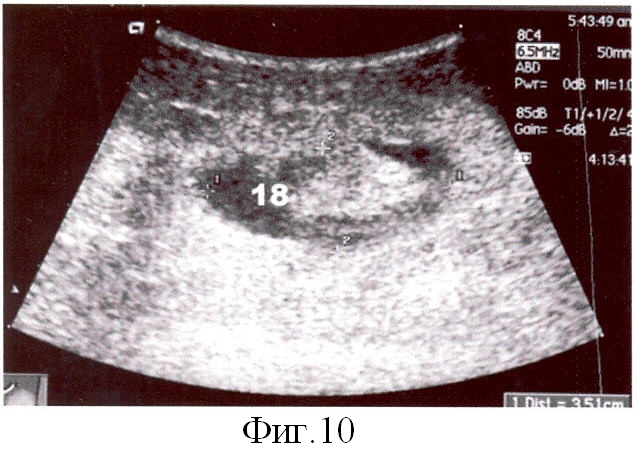

В раннем и отдаленном периодах для контроля за состоянием каналов выполнена эхоабдоминография, показавшая полную облитерацию канальных полостей (фиг.10, поз.18, фиг.11 поз.19). Брюшная стенка при этом была гладкой, без видимых деформаций. Периметр живота в средней трети на протяжении наблюдаемого период оставался в пределах 100±5 см (при исходном размере в 120 см). Вес больной не уменьшился (95 кг при росте 170 см). Рекомендовано соблюдение диеты с целью нормализации ИМТ.